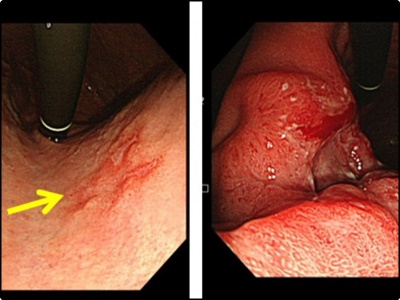

위암 초기증상: 갑작스러운 혈변 또는 대변색의 변화

위암이 진척되는 경우 복부에 덩어리가 느껴지기도 하고 변의 칼라가 흑색으로 나오거나 혈변을 볼 수 있습니다. 이러한 상황이 나타나면 건강에 문제가 생긴 것을 의심해봐야 합니다. 흑색변은 위 점막의 출혈 때문에 출현하는 증상중 한가지 입니다.

위의 출혈은 혈액이 위장에 머물러 있는 시간이 길어지면서 나타나는 증상입니다. 혈액이 장내 세균에 의해 분해가 됨으로써 검은색을 띄는 흑변 증상입니다. 때문에 장출혈과 위염증상 및 위암초기증상에서 출현하는 위출혈은 대변의 색으로 미리감치 구별을 할 수 있습니다.